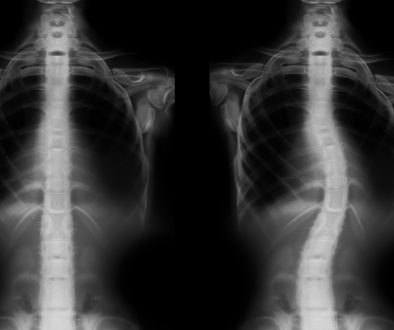

**الانزلاق الغضروفي** يحدث عندما يتمزق الغضروف ويضغط على الأعصاب المجاورة. يتسبب ذلك في آلام شديدة، خاصة في الظهر والرقبة، وقد يمتد الألم إلى الساقين أو الذراعين. تختلف الأسباب من رفع الأوزان الثقيلة بطريقة خاطئة إلى الإصابات الرياضية أو حتى التقدم في العمر.

**التدخل الميكروسكوبي المحدود** هو تقنية جراحية متطورة تهدف لإزالة الجزء المنزلق من الغضروف عبر جرح صغير لا يتجاوز بضع سنتيمترات. يتم ذلك باستخدام ميكروسكوب جراحي يساعد الجراح على رؤية الأجزاء الدقيقة بوضوح، ما يقلل من مخاطر الجراحة التقليدية ويحسن من نتائجها.